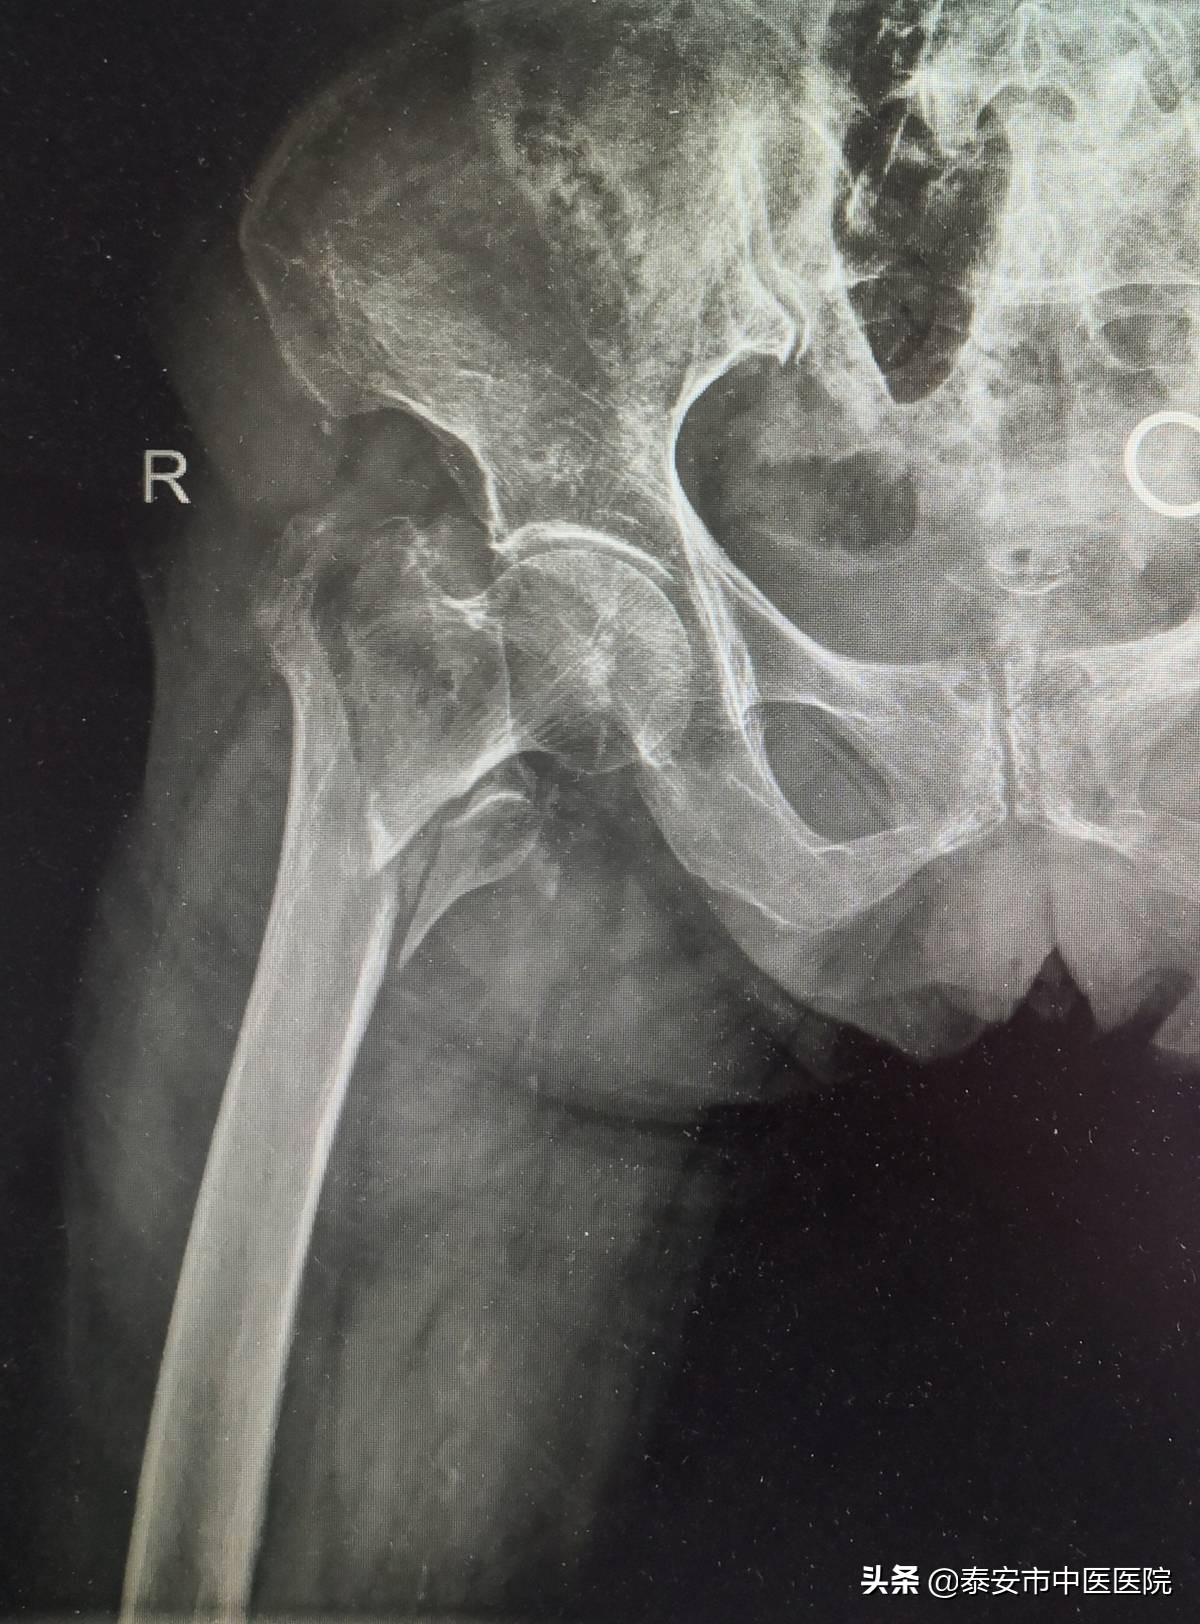

随着社会人口老龄化的发展,中老年人骨折发生率逐年上升,若治疗不当,会出现严重并发症,大大缩短患者的预期寿命,对于此类骨折,保守治疗由于卧床时间太长,易发生深静脉血栓,褥疮,肺部感染等并发症,危及患者生命。该室采用微创经皮内固定治疗股骨粗隆间骨折,具有手术创伤小(切口仅4cm左右),住院时间短,痛苦少,恢复快等优势特点,能让患者迅速恢复正常活动,减轻了患者家庭负担。

微创经皮内固定治疗股骨粗隆间骨折